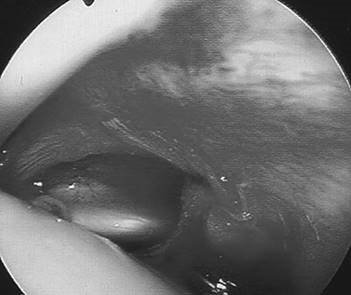

What does his arthroscopy picture show?

The limited view shows a bare lateral wall of the femoral notch, in keeping with a complete ACL rupture.